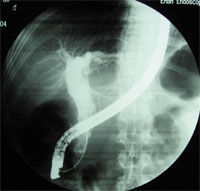

PLG往往無臨床症狀或症狀輕微。診斷主要依靠影像學。對膽囊息肉樣病變的診斷方法較多,如口服膽囊造影、B超、CT、磁共振膽胰管成像(MRCP)、腔內超聲(EUS)等,但目前診斷膽囊息肉最主要的手段仍是B超檢查。

3.內鏡超聲(endoscopicultrasonography,EUS)即經內鏡超聲掃描,是將超聲微小探頭安置在內鏡頂端,探頭為高頻,將內鏡插入消化道,進入十二指腸壺腹後此探頭更接近膽囊,可排除腸氣干擾或膽汁黏稠度等影響。EUS可將膽囊壁分為3層,內層為高回聲的黏膜及黏膜下層,中層為低回聲的肌纖維層,外層為高回聲的漿膜下層及漿膜層。如為息肉樣病變可見清晰的3層囊壁,而膽囊癌則囊壁的3層結構有不同程度的浸潤破壞。早期膽囊癌絕大多數是在結石和息肉等病變的掩蓋下發展的,早期缺乏特徵性聲像圖表現,鑑別困難。而EUS檢查觀察息肉樣病變與膽囊壁之關係,有助於鑑別診斷。朱燕陵等回顧分析了103例非結石性膽囊病變EUS檢查結果並與體表超聲及手術後病理進行比較,EUS檢查診斷正確率為75%,體表超聲為41.4%,EUS對膽囊息肉、膽囊癌、膽囊腺肌瘤診斷符合率為100%,體表超聲為55.6%。Sugiyama認為內鏡超聲(EUS)比BUS更準確,提供的圖像也更清晰。因194例PLG中,EUS判斷的136例非腫瘤性病變平均隨訪2.6年均未發現腫瘤;而BUS判斷的非腫瘤性病變中則有13%為腫瘤。EUS內層的回聲方式為細小聲點(tinyechonicspot)、聲點聚集(aggregationofechogenicspot)、微小囊腫(microcyst)及彗星尾征(comettailartifact)。如EUS證實既無細小聲點與聲點聚集,又無微小囊腫與彗星尾征時,應懷疑為腺瘤或癌腫。兩者無法鑑別,除非已浸潤至肝臟,但若為無蒂病變,則強烈提示為癌腫。結合組織學研究,一個細小聲點表示一群含有膽固醇泡沫的組織細胞,而無回聲區則為腺上皮增生。多個小囊腫和彗星尾征則分別為羅-阿竇增多和膽囊壁內結石所致。Gouma對31例PLG作CT與增強CT對比,CT僅發現14例(45%),而增強CT則為100%。因此,認為凡不增強CT已能發現的病變及增強CT發現的無蒂PLG均應診斷為腫瘤性息肉。有蒂與無蒂的診斷意義很大,20例有蒂PLG中6例為腫瘤(30%),而11例無蒂PLG中10例為腫瘤(91%)。增強CT診斷腫瘤性PLG的敏感性為88%,特異性87%,陽性預測率88%,陰性預測率87%,總準確率87%,結論為增強CT能鑑別腫瘤與非腫瘤性PLG,能可靠地篩選出應予切除的腫瘤性病變。

膽囊息肉病理圖4.CT仿真內鏡(computedtomographicvirtualendoscopy,CTVE)技術自1994年Vining等首次報導以來,國外有不少學者對此技術進行實驗和臨床套用研究。CTVE成像原理為利用計算機軟體功能,將螺旋CT容積掃描獲得的圖像數據進行後處理,重建出空腔器官內表面的立體圖像,類似內鏡所見。膽道CT仿真內鏡技術也已經開始套用於臨床。